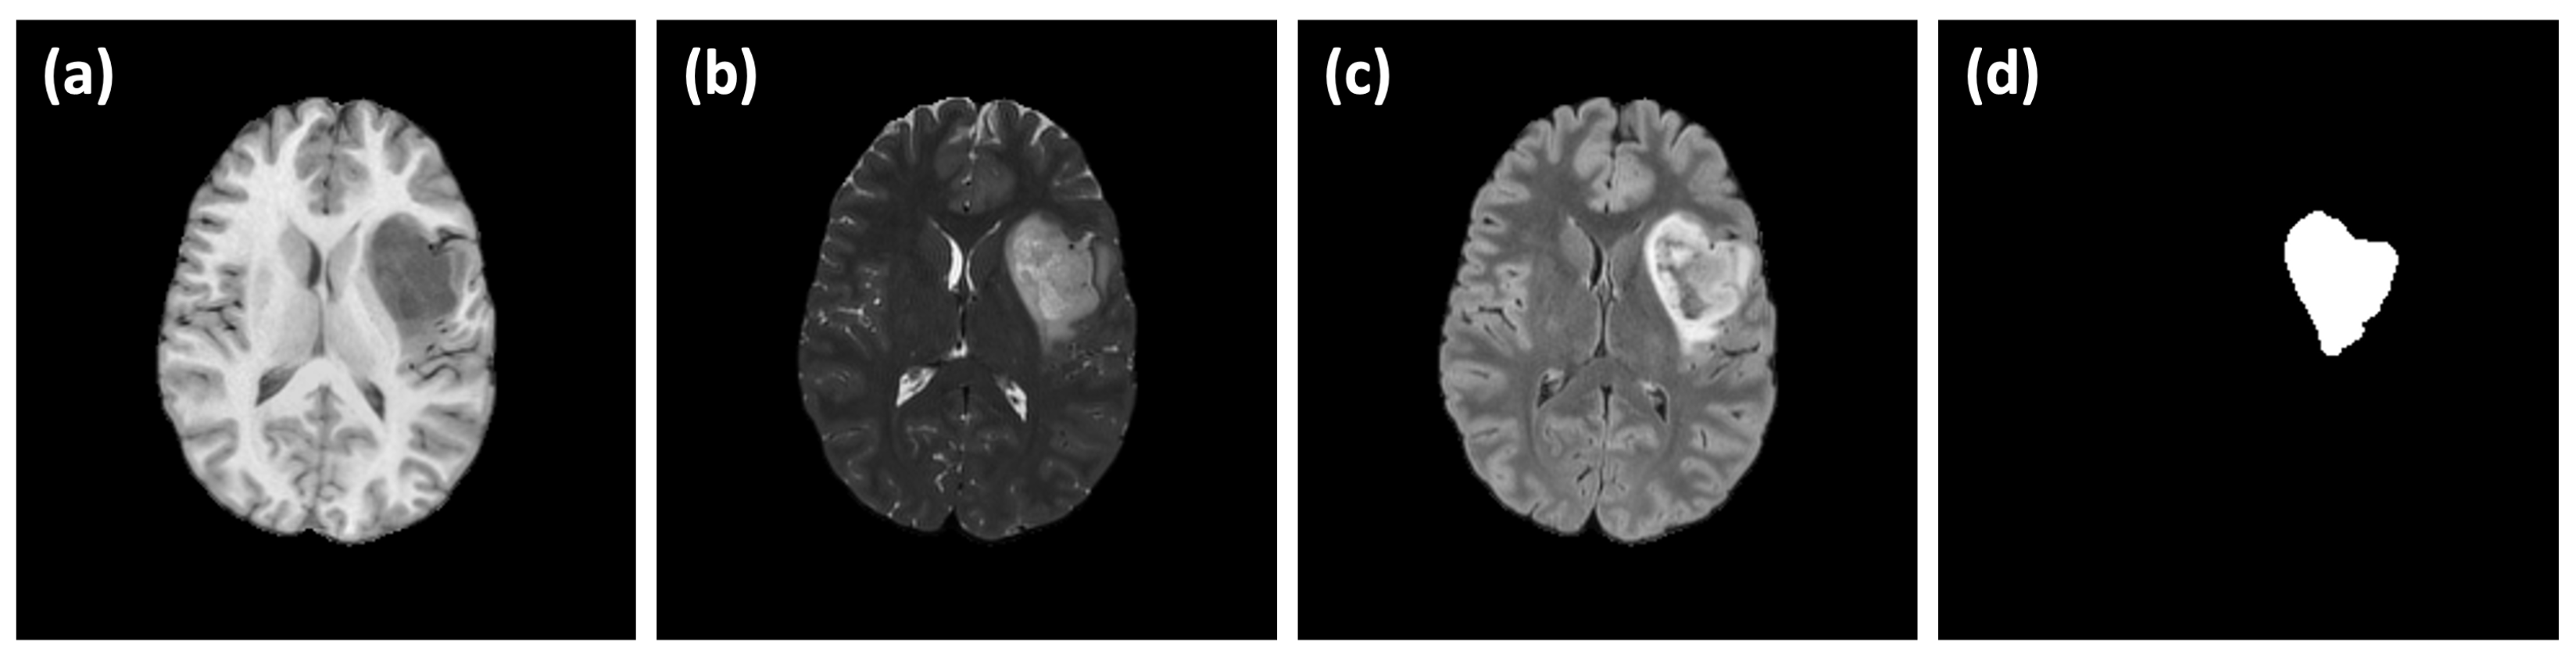

3.1. Image Dataset

4.1. Evaluation of Difference in MRI Sequences